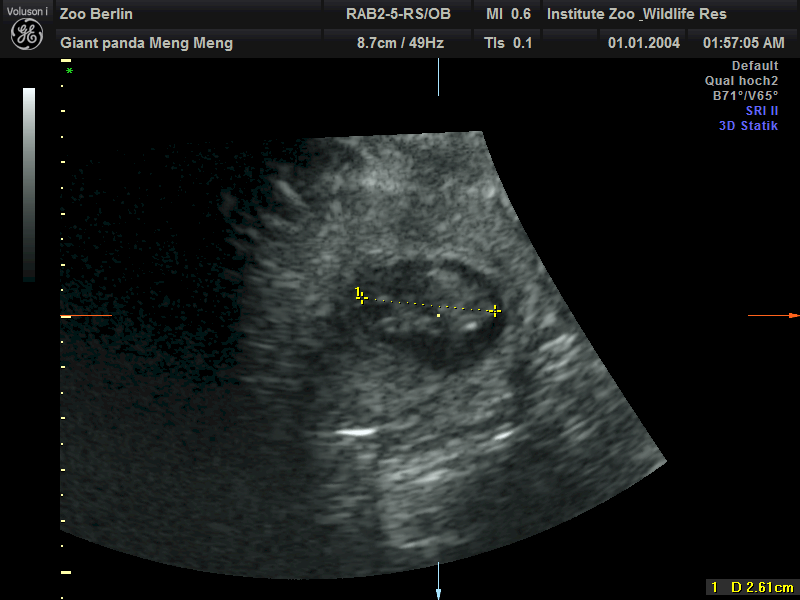

当地时间13日,德国柏林动物园在官网发布公告称,旅居柏林的中国大熊猫“梦梦”确认再次怀上双胞胎,超声检测到两个胎儿心跳。

公告表示,园区在11日的超声检测中确认了这一喜讯。目前两个大熊猫胎儿身长都约为2.5厘米。